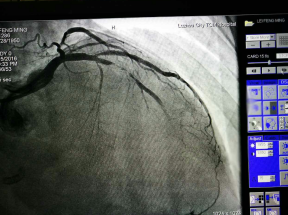

应用切割球囊行冠脉内成形术是治疗支架内再狭窄的最有效方法之一,经过充分的准备,由国家卫计委心血管疾病介入诊治资质医师袁小蓉主刀,通过微创手术将切割球囊送入冠状动脉内,切割支架内再狭窄部位,再次成功地开通了周阿姨心脏血管,术后症状完全消失。目前周阿姨已经康复出院,随访情况良好。

术后